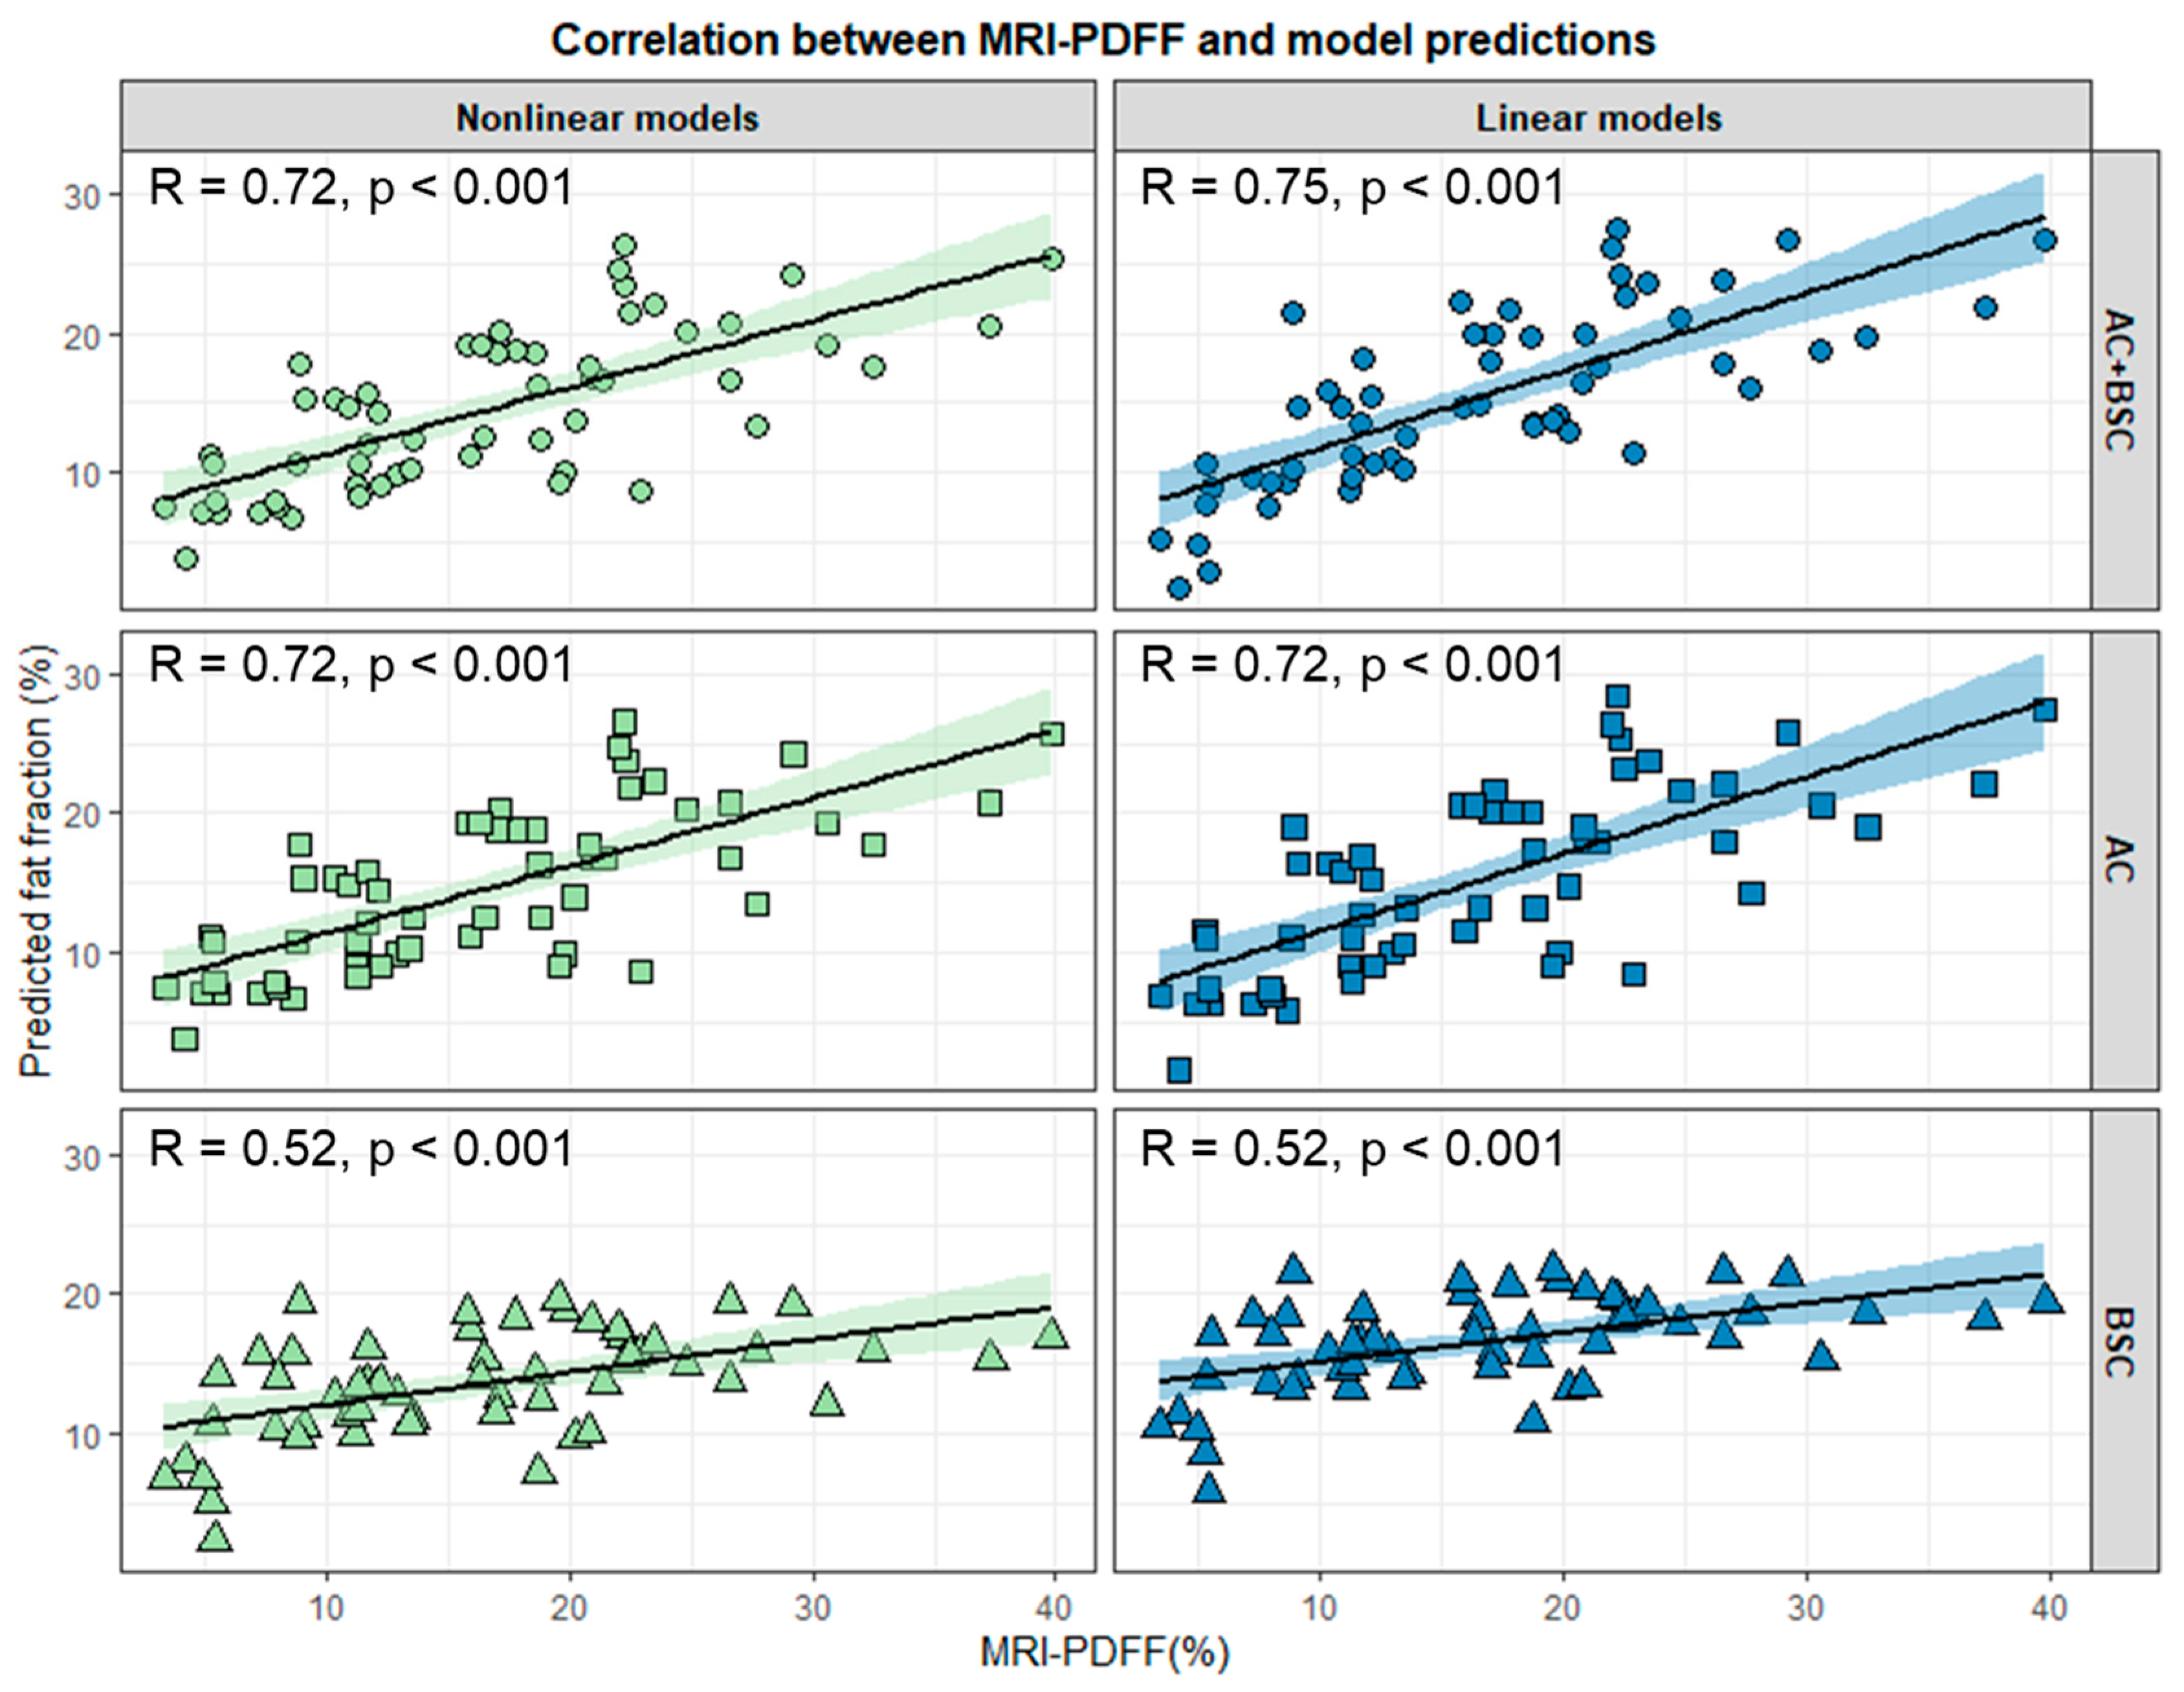

3.3. Evaluation of Models’ Performance in the Test Set

3.4. Grid Search of Ultrasound Parameters